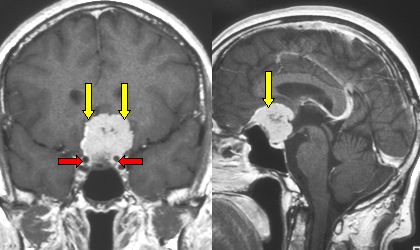

O meningioma é um dos tumores cerebrais primários mais comuns e é diagnosticado com maior frequência em mulheres. Essa prevalência feminina tem sido historicamente associada à influência dos hormônios sexuais.

A análise abrangente de dados de mais de 10 milhões de mulheres americanas demonstrou que as usuárias de medroxiprogesterona injetável (dMPA) apresentavam um risco 143% maior de meningioma em comparação com o grupo de controle. Notavelmente, esse risco aumentou mais de três vezes com o uso contínuo do contraceptivo por mais de quatro anos, sendo as mulheres que iniciaram a terapia após os 31 anos as mais vulneráveis.